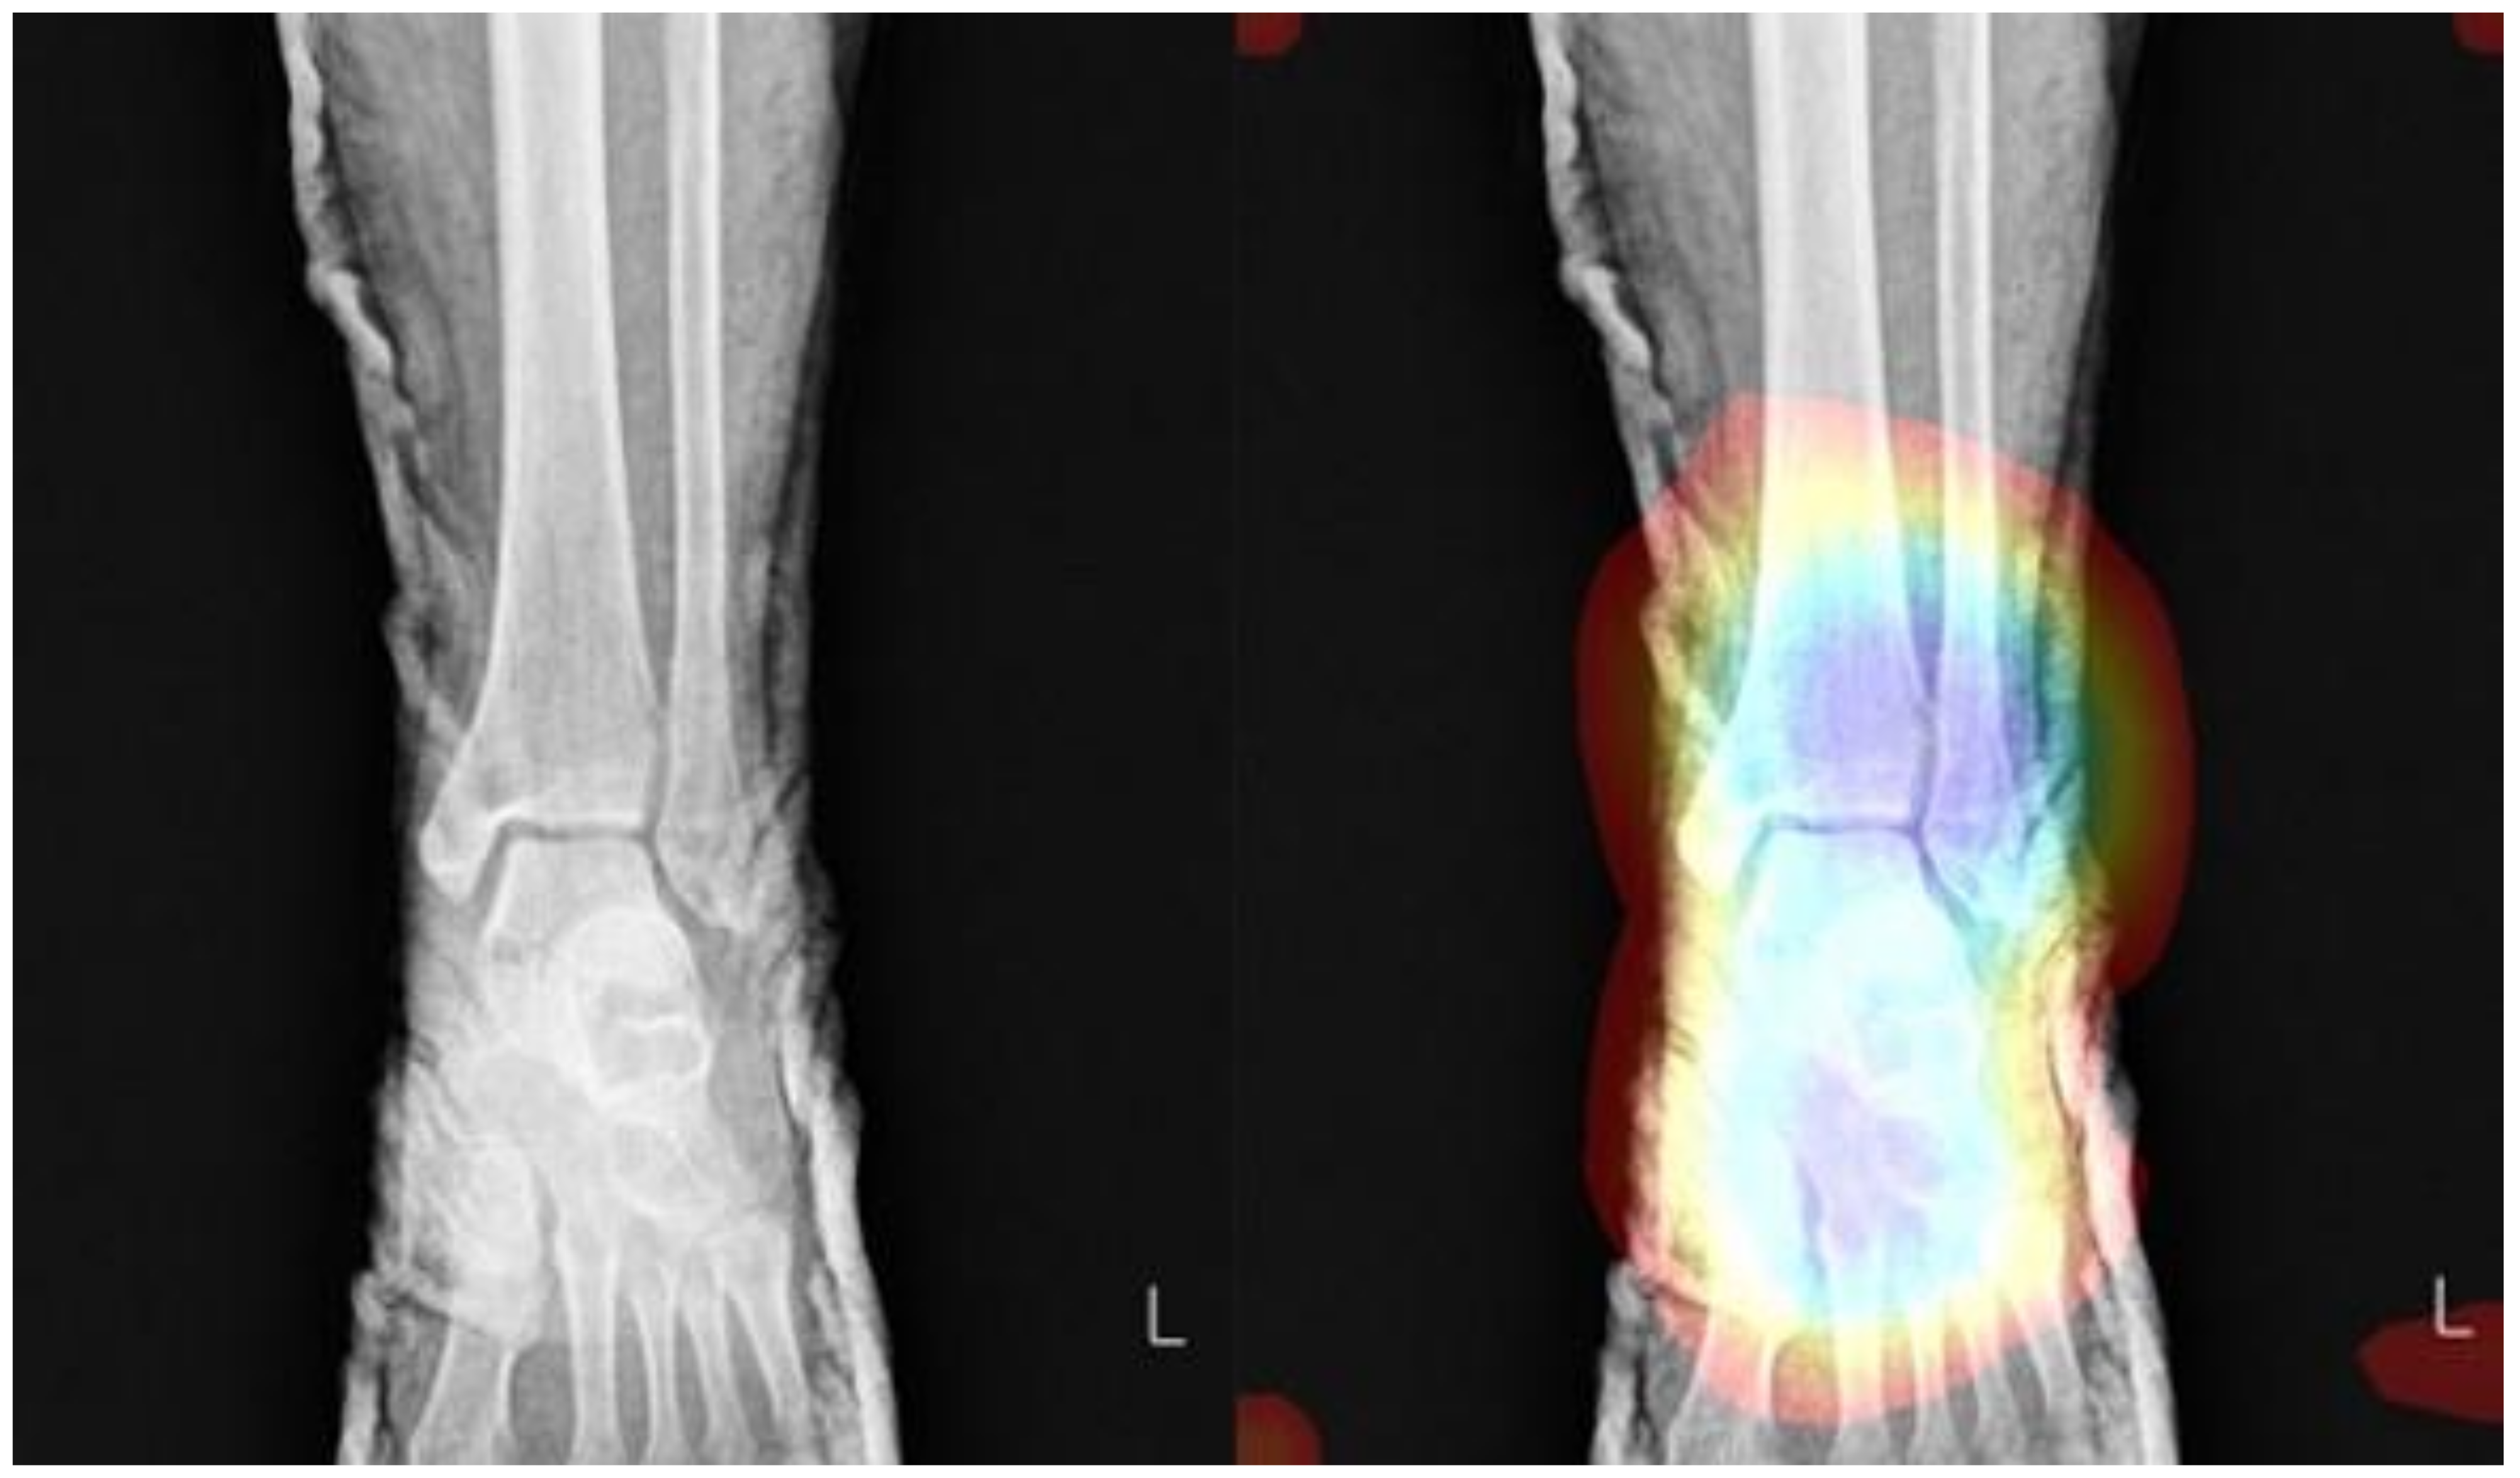

Detecting Ankle Fractures in Plain Radiographs Using Deep Learning with Accurately Labeled Datasets Aided by Computed Tomography: A Retrospective Observational Study

2.1.1. Dataset Preparation